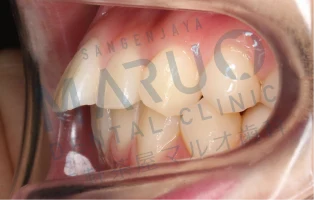

治療前

上の前歯が前に出ていることと歯のでこぼこを治したいとのことでした。

治療中

表側に装置をつける矯正を選択されました。上下左右の大人の歯を1本ずつ抜いて歯を並べ、前歯を後方に動かすスペースを確保しました。

動的治療終了時

動的治療期間は約2年6ヶ月でした。上の前歯の傾斜は改善し、歯のでこぼこは解消され、患者様に満足いただける結果となりました。

| 主訴 | 上の前歯が前に出ている 歯のでこぼこ |

|---|---|

| 診断名 | 上顎前突 叢生 |

| 年齢 | 13歳 |

| 治療に用いた主な装置 | マルチブラケット装置 |

| 抜歯部位 | 上下両側第一小臼歯 |

| 治療期間 | 2年6ヶ月 |

| リスク、副作用 | むし歯や歯周病、歯根吸収、治療後の後戻りの可能性があります |